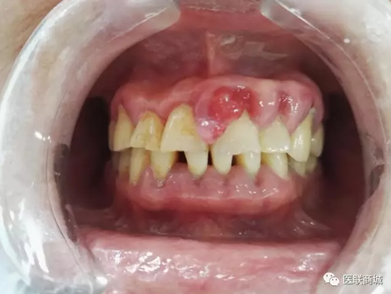

口腔衛(wèi)生狀況較差,牙石(++),軟垢(++),全口牙齦紅腫增生明顯,11、21、22、23牙齦增生明顯,11、21齦乳頭呈菜花樣增生,質(zhì)軟,界清,觸痛(-),易出血,全口PD=5-7mm,下前牙舌側(cè)GR=1-2mm,咬合關(guān)系基本正常,未見明顯咬合創(chuàng)傷。